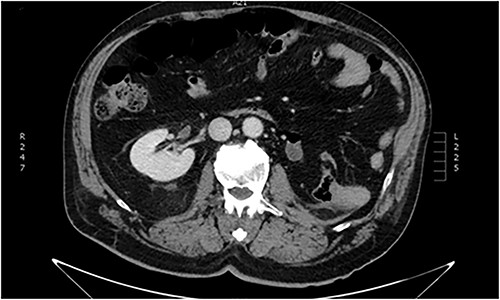

Imaging investigation with thoracic x-ray revealed 9th to 11th posterior rib fractures, as well as small pneumothorax on the right rib cage. Abdominal ultrasound revealed no internal bleeding or fluid within the peritoneal cavity and spaces, but an injured ectopic left kidney was detected within the pelvic cavity, previously unbeknownst to the patient. Further imaging with abdominal and pelvic computed tomography (CT) scan confirmed the occurrence of a grade III laceration (according to the American Association of the Surgery of Trauma—AAST renal injury grading scale) of the ectopic kidney (Figs. 1 and 2).

Abdominal CT imaging. Ectopic (pelvic) left kidney. Presence of grade III laceration without collecting system rupture or urinary extravagation.